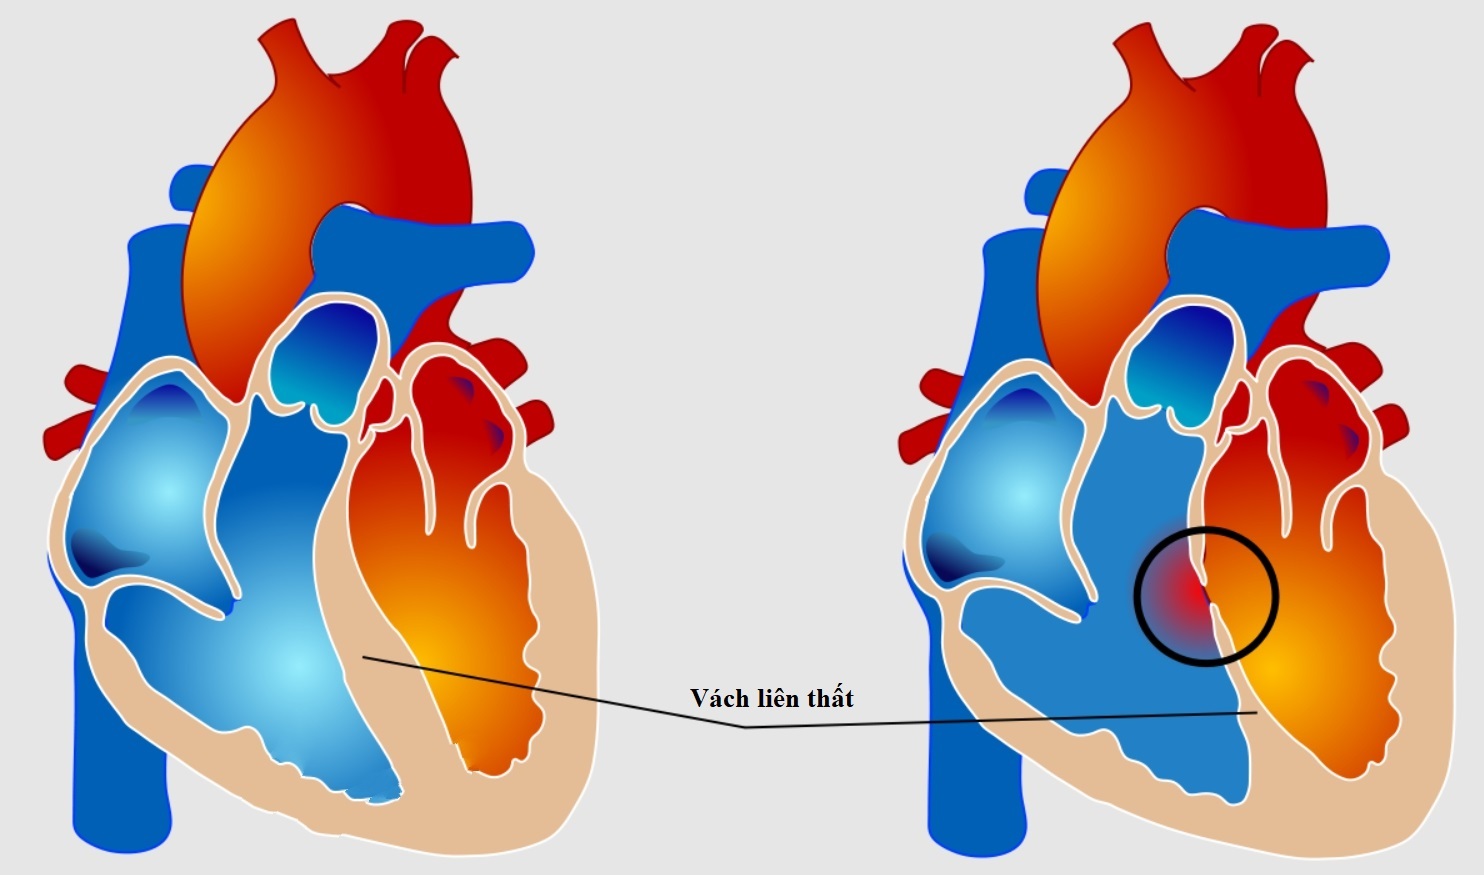

1. Thông liên thất

– Thông thường khi trẻ sinh ra, vách này không có lỗ thông vì vậy không cho phép máu của hai tâm thất hòa trộn với nhau. Trong vách liên thất là nơi có phần đầu quan trọng của hệ thống thần kinh dẫn truyền xung động từ nhĩ đến các phần cơ thất.

– Thông liên thất là bệnh tim bẩm sinh thường gặp nhất trong tất cả các bệnh tim bẩm sinh chiếm 15-20% tất cả các bệnh tim bẩm sinh, đó là chưa kể đến các thông liên thất trong các bệnh tim bẩm sinh có tím phức tạp.

+ Thông liên thất lỗ nhỏ (Bệnh Roger): Đường kính lỗ thông < 1/3 so lỗ van động mạch chủ (ĐMC) hay < 0,5cm2, luồng thông ít từ thất trái qua thất phải lên động mạch phổi (ĐMP) nên gây rối loạn huyết động học không đáng kể, chưa ảnh hưởng đến chức năng phổi và tim.

+ Thông liên thất lỗ vừa: còn gọi là TLT hạn chế, đường kính lỗ thông > 1/3 và < lỗ van ĐMC. Có rối loạn huyết động học đáng kể vì luồng shunt từ tâm thất trái sang tâm thất phải vào ĐMP, lên phổi làm tăng lưu lượng tuần hoàn lên phổi rồi về nhĩ trái xuống thất trái và tăng gánh tâm trương thất trái diễn tiến dẫn đến tăng áp động mạch phổi rồi dần dần ảnh hưởng thất phải.

+ Thông liên thất lỗ lớn: còn gọi là TLT không hạn chế, lỗ thông > lỗ van ĐMC. Vì lỗ thông lớn và luồng thông nhiều

nên gây rối loạn huyết động nặng nề với tặng tuần hoàn phổi, tăng gánh thể tích thất trái, tăng áp động mạch phổi và tăng gánh thất phải. Giai đoạn đầu áp lực thất trái cao hơn áp lực thất phải lúc đó luồng thông từ trái sang phải. Bệnh diễn tiến nhanh gây ảnh hưởng đến chức năng thất trái khi áp lực hệ phổi cao hơn hệ chủ gây đảo chiều shunt phải-trái tạo nên phức hợp Eisenmenger, tăng áp động mạch phổi cố định.

+ Thông liên thất quanh màng: 70-80%

+ Thông liên thất phần buồng nhận: 3-8%

+ Thông liên thất phần cơ bè: 5-20%

+ Thông liên thất phần thoát / phần phễu: 5-7%